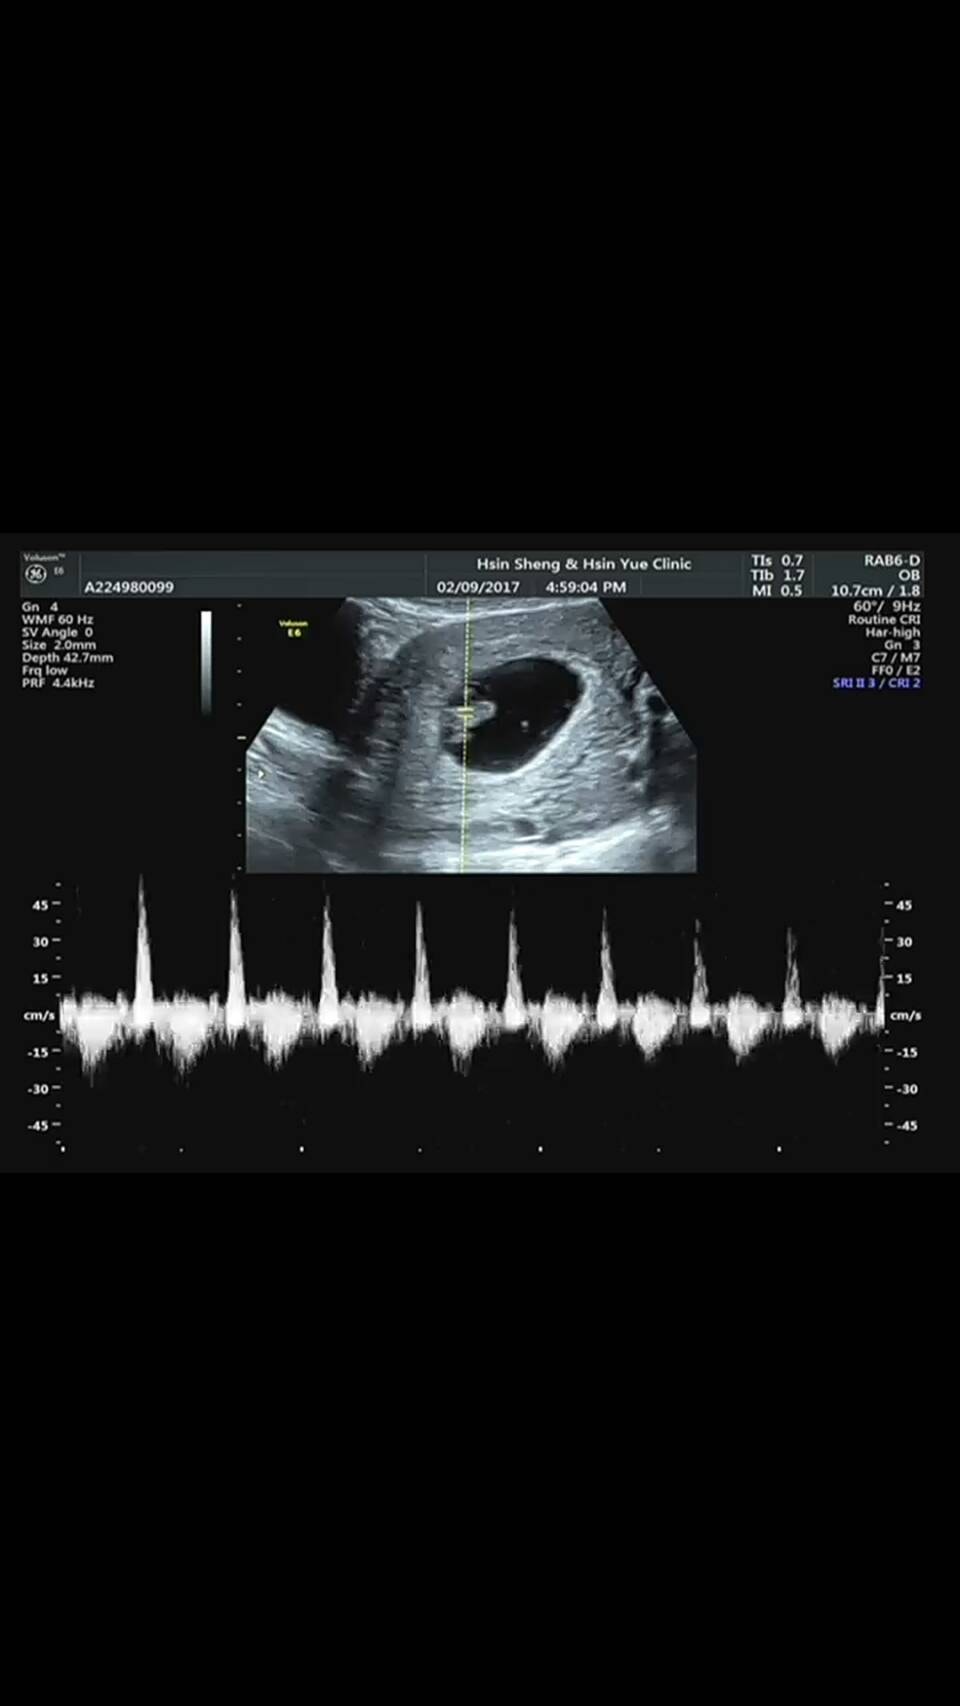

老公帶著我和芊芊一起來婦產科檢查

我們找上次幫我們驗的醫生

她也很訝異地說~天啊!!妳竟然懷孕了

照超音波時,聽到寶寶那強而有力的心跳聲更是讓我不由自主地流下眼淚

(請幫我放五月天的一顆心噗通噗通的狂跳~)

醫生說這寶寶非常健康,心跳聲強而有力且規律

照完超音波後,醫生開了安胎藥和葉酸讓我備著

以前都照不到,現在一照就有心跳而且兩個多月